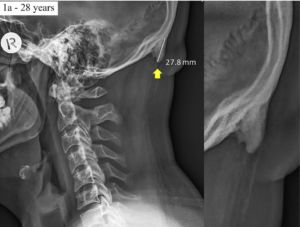

Enlarge / An elongated EOP.The bone spurs jut off of what’s known as the exterior occipital protuberance (EOP) of the cranium. That is the purpose in the back of the pinnacle the place necessary ligaments that run alongside the backbone connect, as do neck muscle tissues. The EOP might be outstanding—should you really feel the again of your personal head, it’s possible you’ll really feel a tough lump the place the EOP is. It tends to be extra noticeable in males, and forensic scientists have used the EOP’s measurement to find out the gender of broken corpses and human stays.

Like all of the locations within the physique the place ligaments and muscle tissues connect to bones, overuse and tensile stress can set off additional bone progress, forming enthesophytes. These are irregular bony projections, aka bone spurs. Within the examine, Shahar and his co-author, Mark Sayers, name these EOP bone spurs, elongated EOPs, or EEOPs.

No matter they’re known as, crucial factor to learn about them is that they’re completely not necessary. Whereas their presence could also be a delicate trace that an individual is straining their neck muscle tissues an excessive amount of, they’re in any other case inconsequential to well being; they don’t trigger ache or every other symptom. They’re unnoticeable until you particularly search for them in medical photographs—which medical doctors have a tendency to not do as a result of, properly, there’s actually no level.